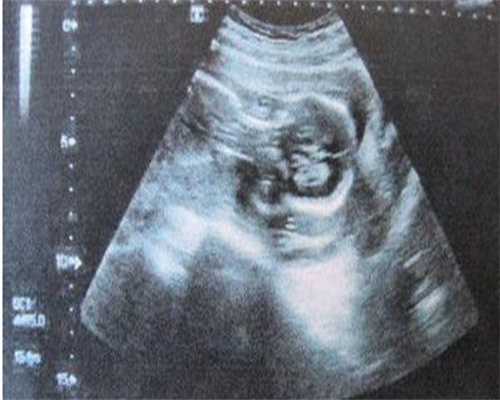

1、广东供卵试管小孩哪里公司好?2026广东试管婴儿费用明细?试管婴儿已经成为很多不孕不育夫妻的最后救命稻草,在广东地区也有很多能做试管婴儿的医院,如果要做试管婴儿的话,一定要提前了解一下广东各医院试管婴儿的价格,如果不了解的话就不知道到底需要准备多少的费用,针对大家的问题,柚喜网特地带来了广东各医院试管婴儿的费用明细,供大家参考。针对这些疑问,在文中就能了解到详情。

2、2026年在广东做试管婴儿的大致费用在1-10万左右不等,一般来说,包括促进排卵的药物、手术费、实验室费用等,每个项目的费用最低一百多,最高在几千到上万不等,还需要根据个人的实际情况来判断,手术对象的年龄,医院医生和技术使用的总体水平才能确定最终的费用。

3、在广东做试管婴儿的家庭钱花在了各项检查,促排卵等项目上,各个项目的费用不等,这里就有一份网友关于在广东做试管婴儿的各个项目费用清单明细: